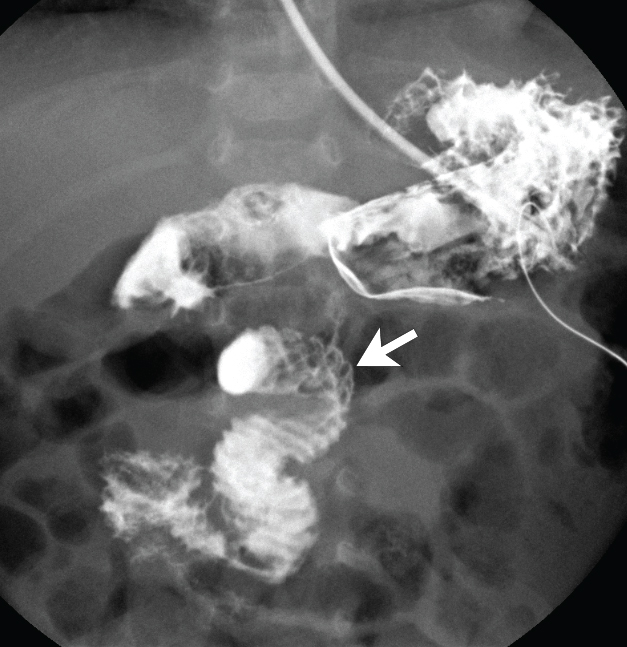

Figure 1B: Fluoroscopic frontal view of mid abdomen obtained during an upper gastrointestinal series demonstrates a "corkscrew" configuration to the duodenum in this patient with malrotation and midgut volvulus. The duodenojejunal flexure (arrow) is abnormally positioned; it is lower than the duodenal bulb and is not left of midline.

The "corkscrew sign" (Figure 1B) refers to the twisted configuration of the proximal small bowel loops seen on upper gastrointestinal (UGI) in the setting of malrotation with midgut volvulus. The "whirlpool sign" is it sonographic counterpart and consists of a swirling pattern of flow on color Doppler ultrasound images created when the superior mesenteric vein (SMV) and the mesentery wrap around the superior mesenteric artery (SMA) (Figure 1A).